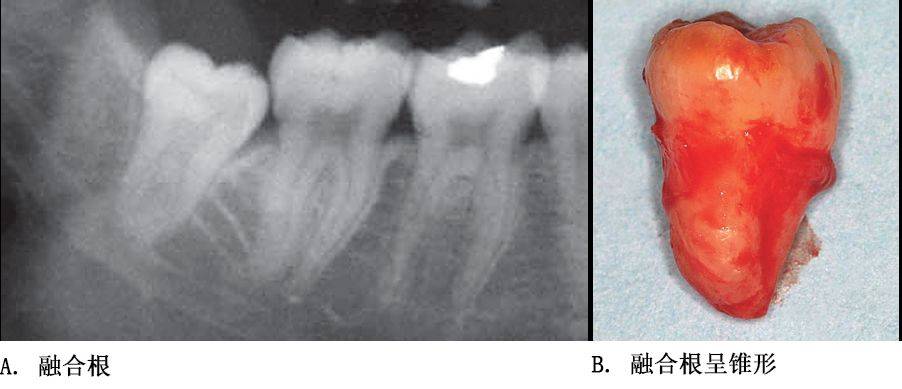

单根牙、根分叉不大者、合并根、融合根、特短根、锥形根阻力较小。若根尖区向远中弯曲、无弯曲或根尖未形成,则阻力也较小。

根部阻力较小的智齿形态